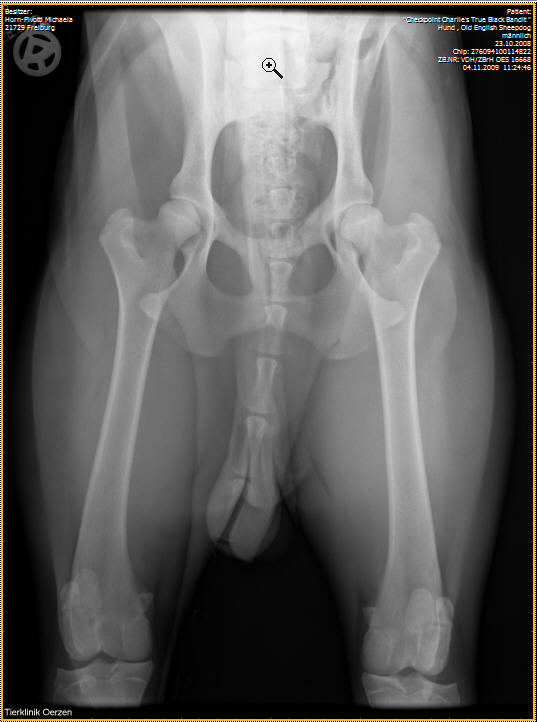

Röntgenaufnahmen HD/ED “Checkpoint Charlie’s True Black Bandit”